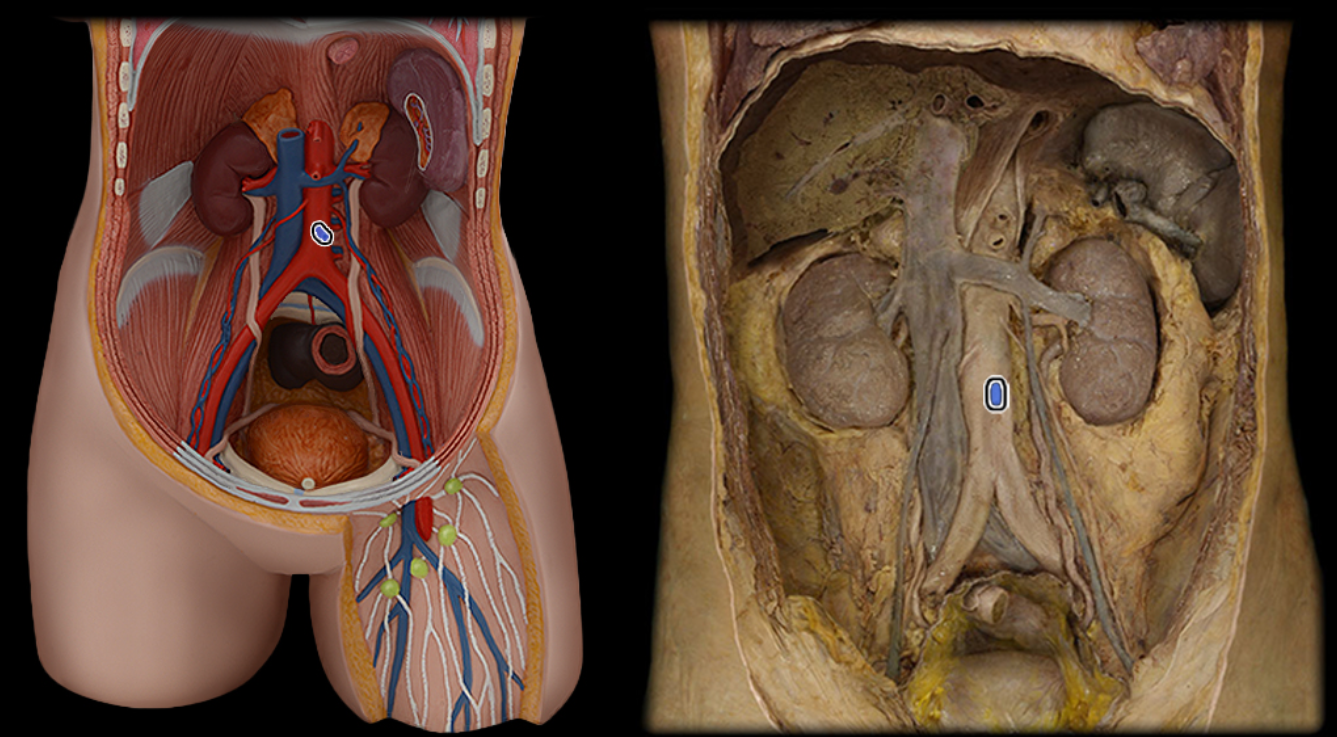

Abdominal aorta

Common iliac a.

Common iliac v.

External iliac a.

External iliac v.

Femoral a.

Femoral v.

Gonadal a.

Gonadal v.

Inferior vena cava

Lumbar a.

Lumbar v.

Renal a.

Renal v.

Superior mesenteric a.